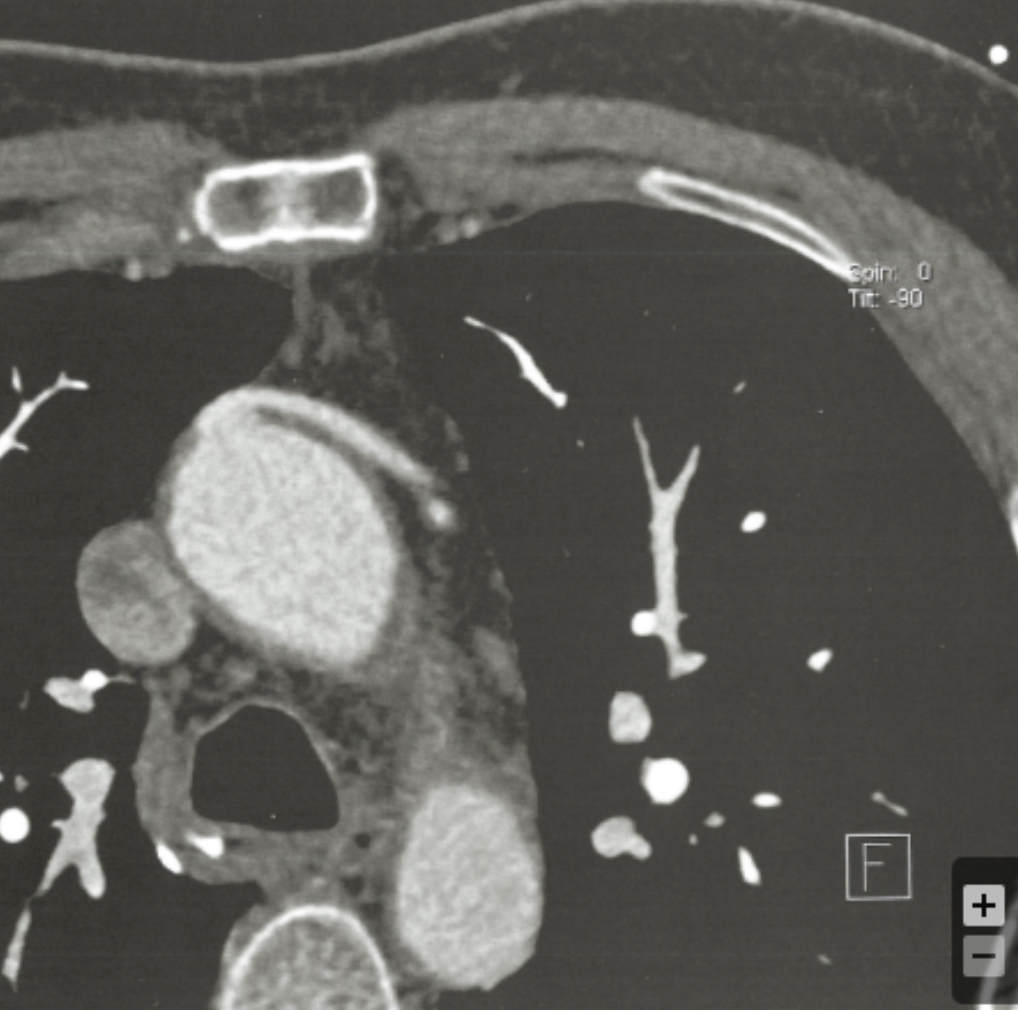

Describe the findings:

Vein Graft (proximal anastomosis)

??Conus branch??